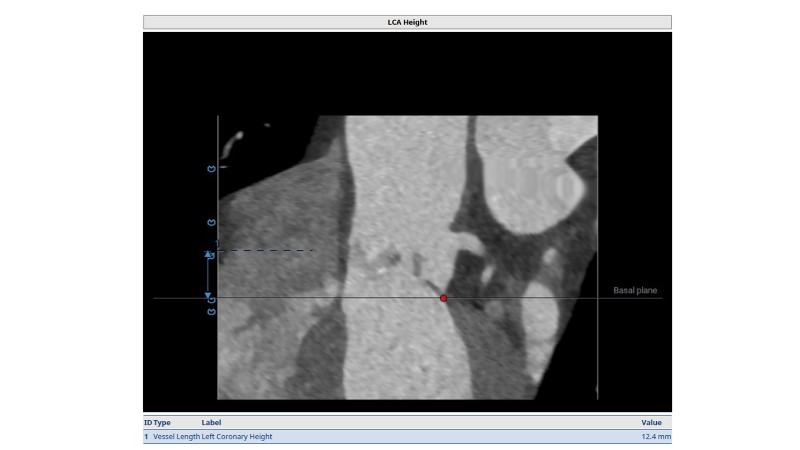

Discover how thoughtful index valve selection and implantation techniques can shape the long-term management of patients undergoing TAVI. This PCR London Valves 2025 session highlights treatment considerations for low- and intermediate-risk patients, explores how valve choice affects the feasibility of future interventions, and examines strategies to achieve optimal and durable clinical outcomes. Follow real patient case with imaging analysis, hemodynamic insights in small annuli, and discussions on planning for future revalving and coronary access.